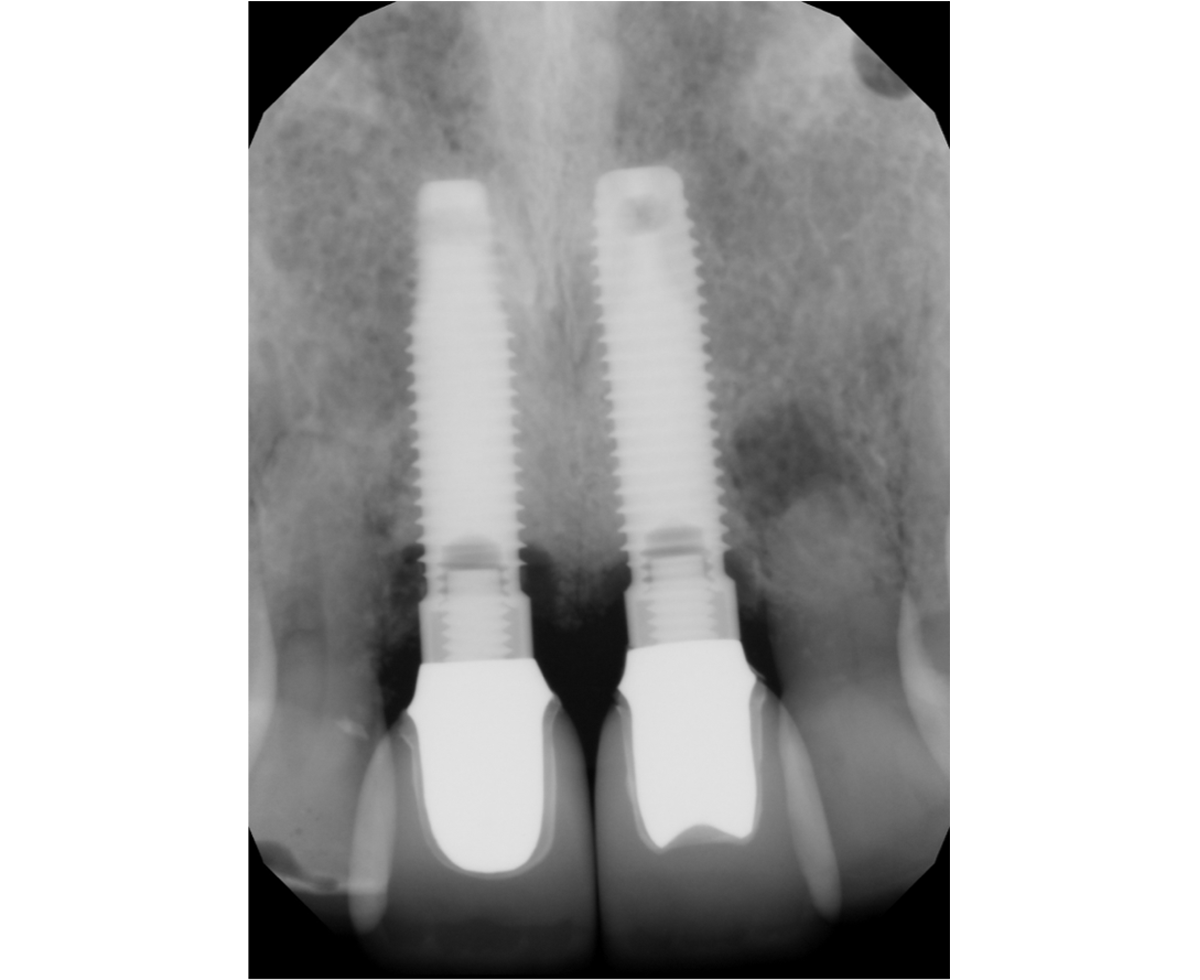

Implantes

Son procedimientos clínicos comunes y complejos, que se realizan constantemente en nuestra práctica. Normalmente consiste en la colocación de aditamentos de titanio, que sustituyen las raíces de dientes ausentes.

Este tipo de procedimiento involucra dos partes. Una es la colocación quirúrgica del perno en el hueso que es ejecutado, generalmente, por un odontólogo periodoncista o cirujano dental, y la otra es la parte rehabilitadora, que es la colocación de la corona sobre el tornillo, que lo realiza el odontólogo restaurador. Para que un implante dental se vea como un diente natural se deben cumplir ciertos parámetros, entre ellos: